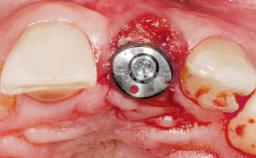

A 30-year-old female patient had lost tooth 21 and was referred to our clinic for consultation and treatment. Due to advanced apical infection, tooth 21 had been extracted two months earlier at another clinic and an acrylic-resin tooth had been bonded to the adjacent teeth. The patient desired implant treatment to avoid any damage to the adjacent natural teeth. While the patient had no history of any systemic disorder, she was a heavy smoker and exhibited medium to advanced periodontitis in the entire jaw. After the initial treatment to achieve a pocket probing depth of less than 4 mm and no bleeding on probing, a decrease in the height of the papillae mesial and distal to the extraction site and overall gingival recession were observed.

| Bone Augmentation | Horizontal|Staged |

| Augmentation Materials | Autogenous chips|Membrane |